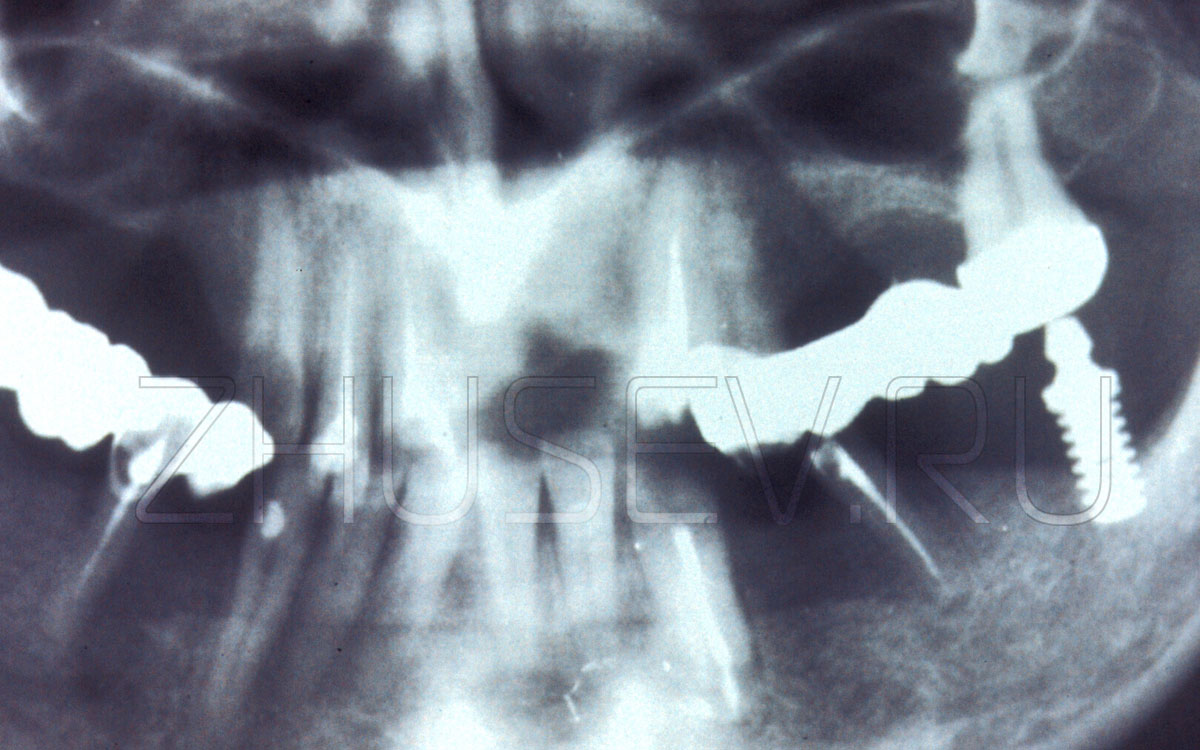

А эти имплантаты-гвоздики молотком забивались в челюсть в любых местах и под любым углом.

Вариация на тему цилиндрического имплантата с канавками, в которые должна была врастать кость.

Редкий экземпляр эндосто-субпериостального имплантата.

Очень часто слесарное-строительные технологии прямиком переносили в операционную. Правда, очень быстро стало ясно, что кость это не стена в квартире и не входная дверь!